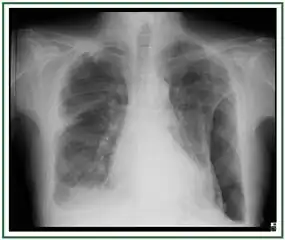

If a fibrothorax is severe, the thickening may restrict the lung on the affected side causing a loss of lung volume.[7] Additionally, the mediastinum may be physically shifted toward the affected side.[3] A reduction in the size of one side of the chest (hemithorax) on an X-ray or CT scan of the chest suggests chronic scarring.[6] Signs of the underlying disease causing the fibrothorax are also occasionally seen on the X-ray.[6] A CT scan may show features similar to those seen on a plain X-ray.[7] Lung function testing typically demonstrates findings consistent with restrictive lung disease.[6]

Extensive left-sided fibrothorax

Chest radiograph displaying inhomogeneous opacification of the left half of the chest that is fibrothorax